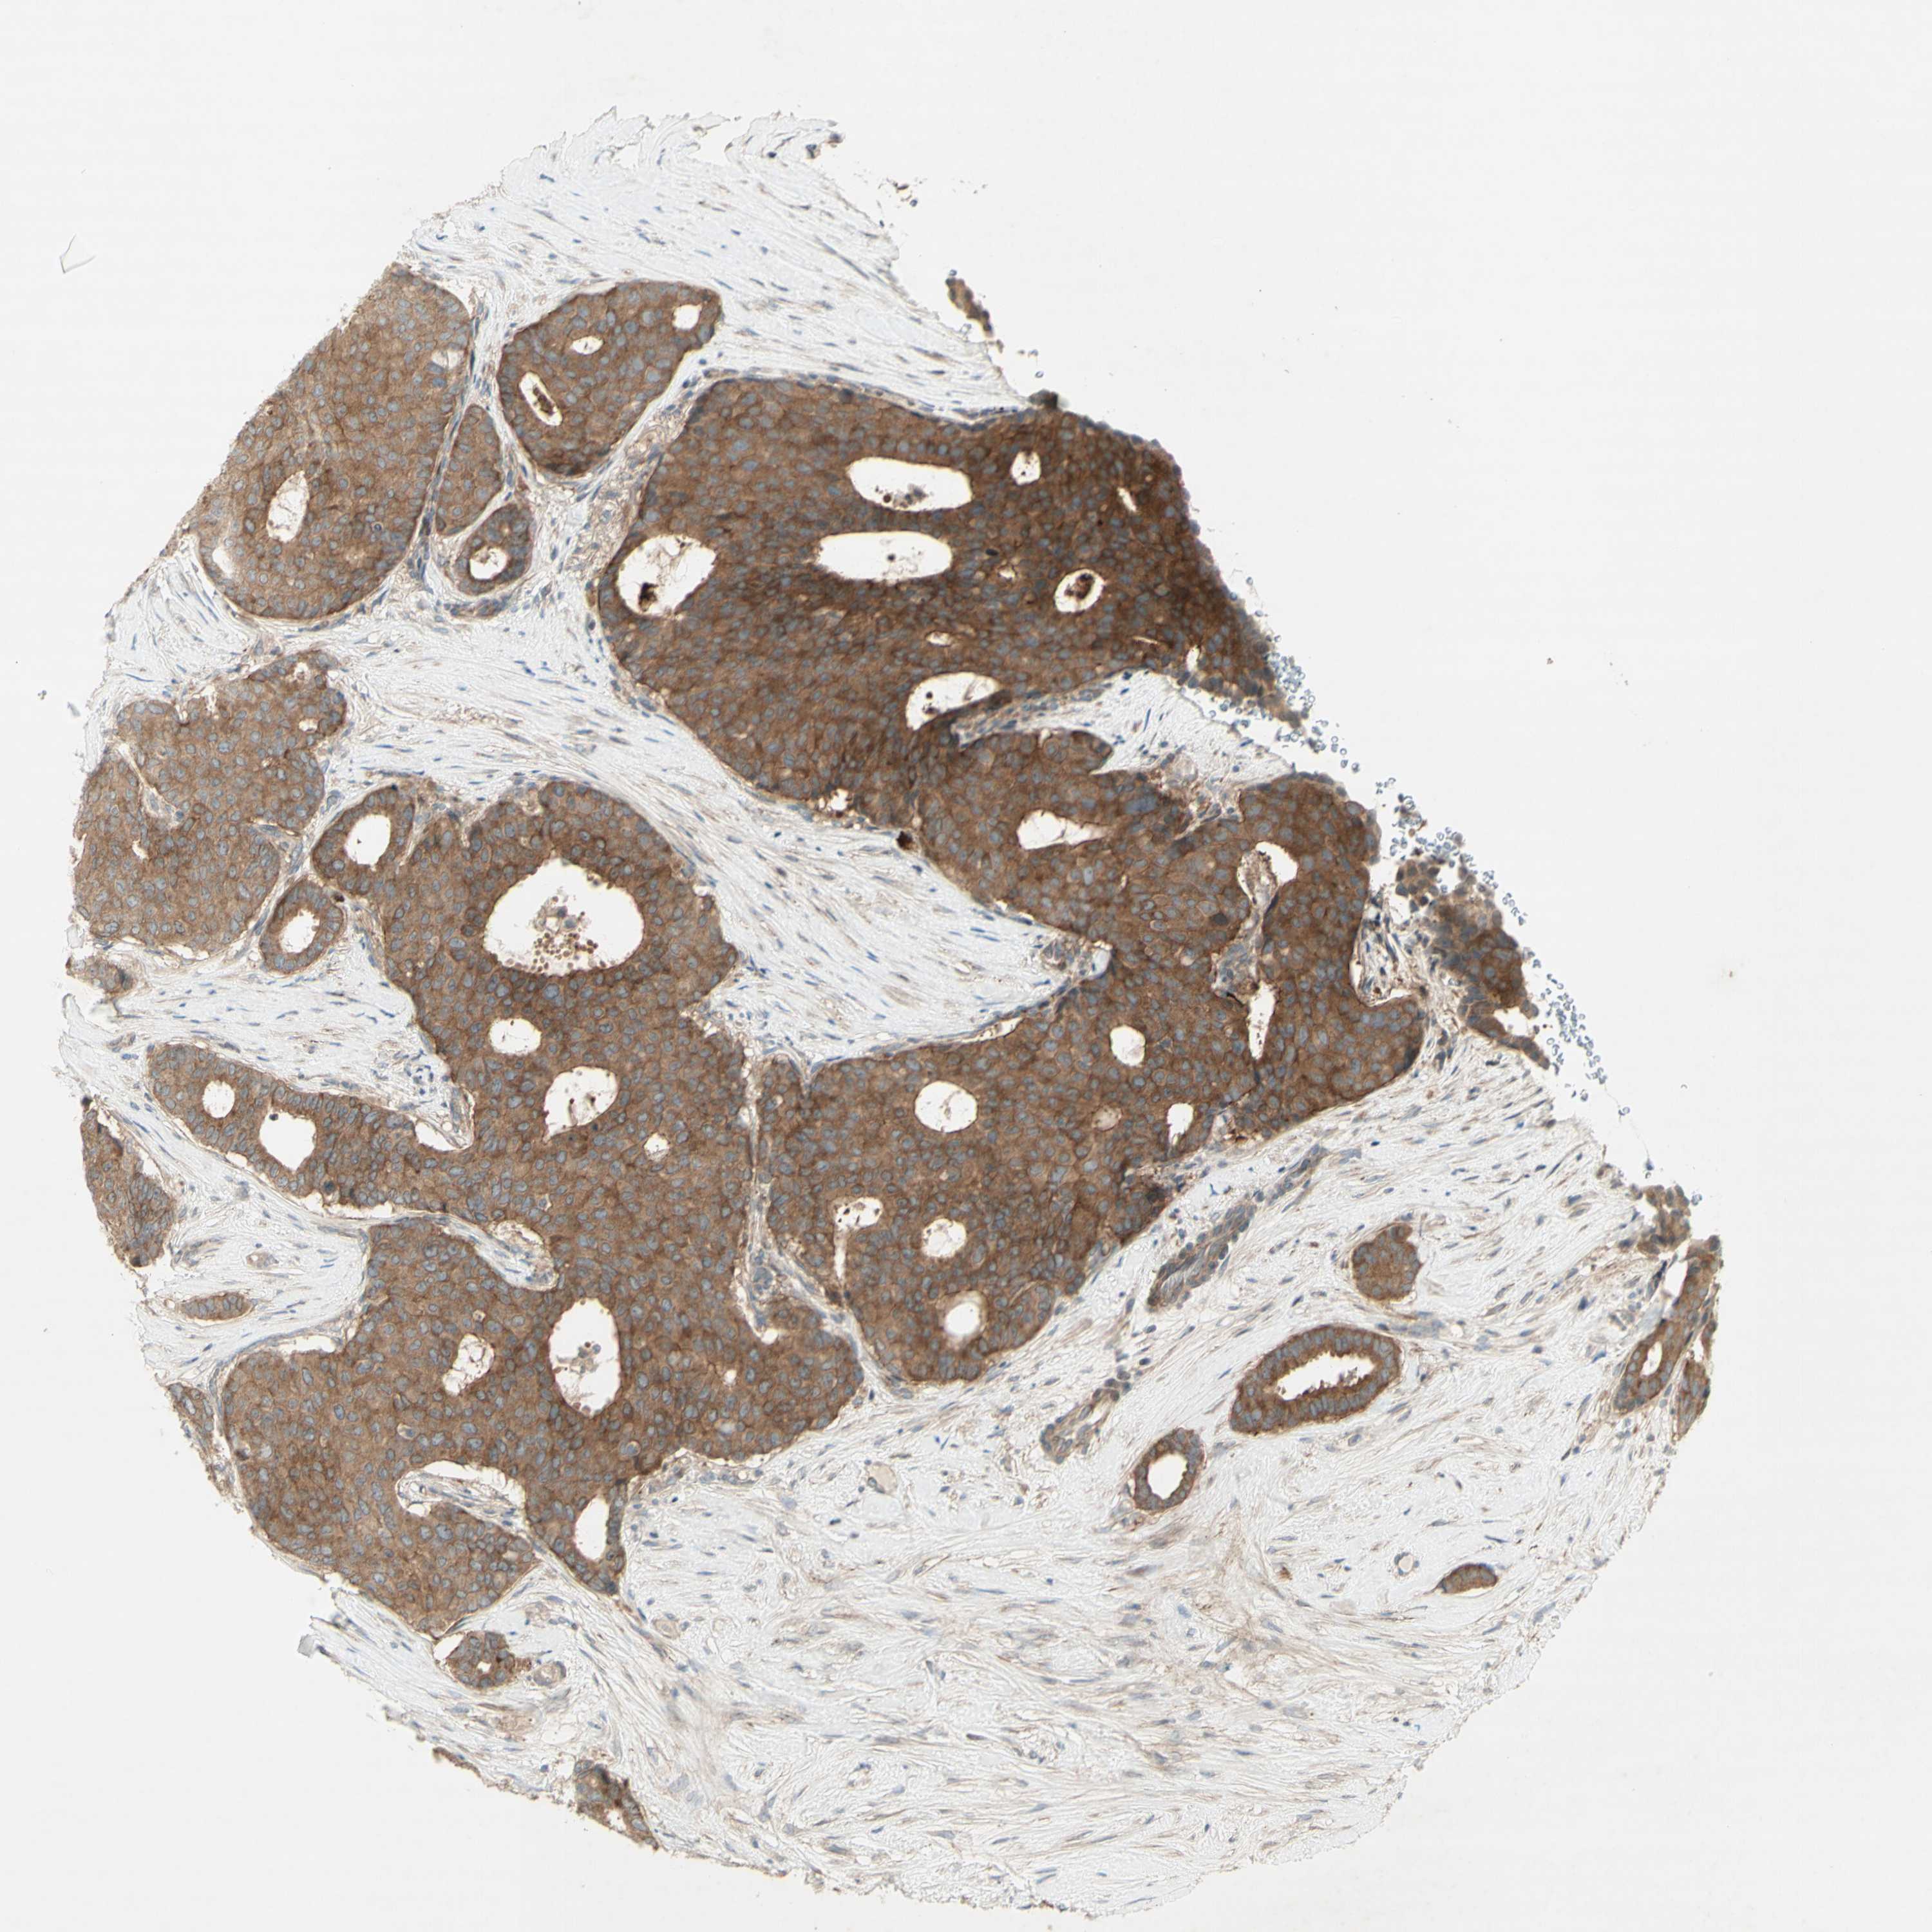

BRCA TCGA BRCA VALIDATION PROTEIN EXPRESSION